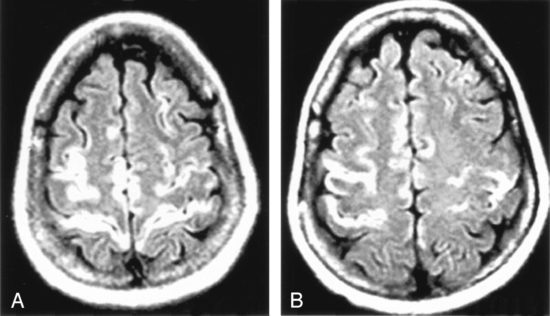

Герпес может проявляться не только как «пузырьки на губах». Некоторые типы вируса могут вызывать: воспаление глаз (герпетический кератит), воспаление мозга (энцефалит), поражения кожи и слизистых, осложнения у новорождённых и людей с ослабленным иммунитетом.